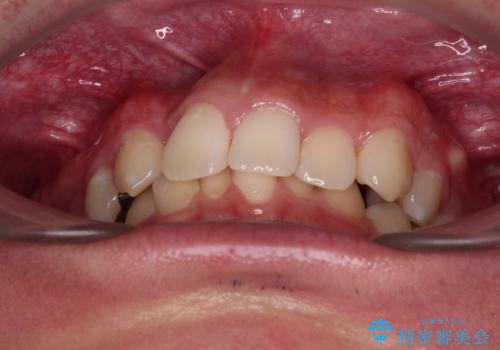

- 「前歯のデコボコが気になる」「前歯の中心がずれていて気になる」とご相談に来られた患者様の症例です。

診察の結果、上下の歯が並ぶためのスペースが不足しており、特に上顎右側の側切歯が内側(口蓋側)に転移していたため、正中が大きく右にずれている状態でした。